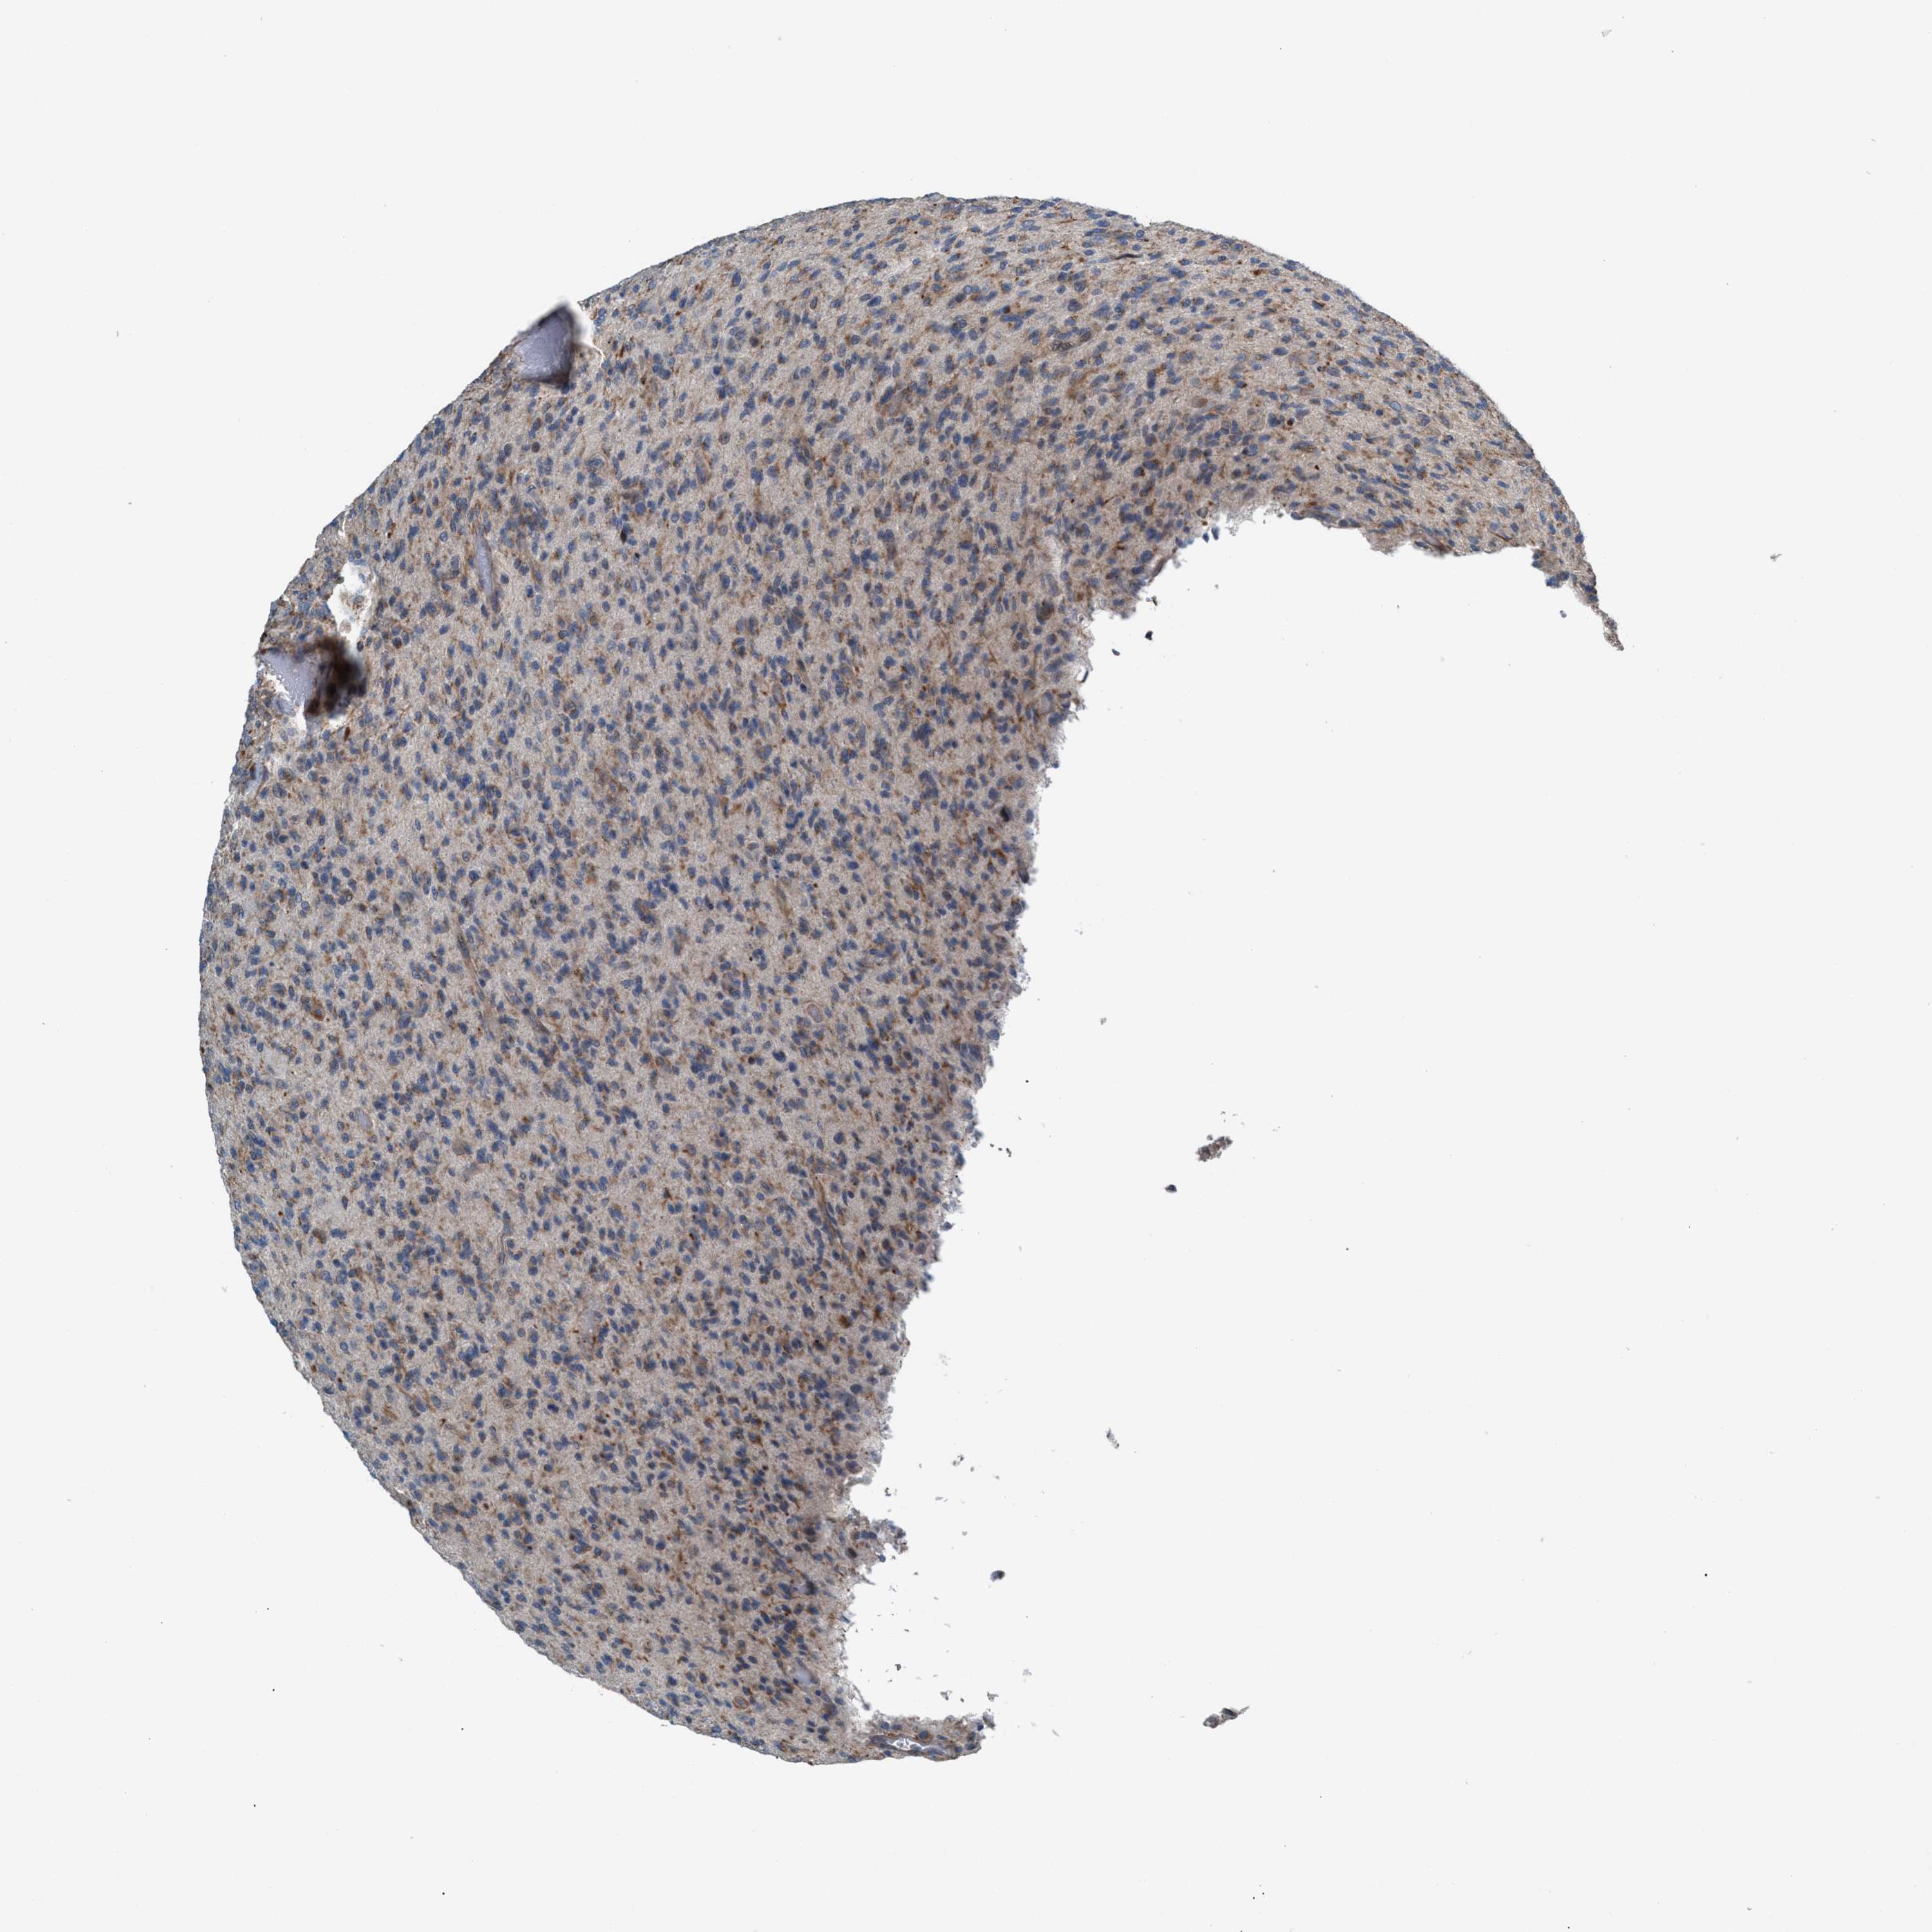

GLIOMA - Protein expressioni

A mouse-over function shows sample information and annotation data. Click on an image to view it in a full screen mode. Samples can be filtered based on level of antibody staining by selecting one or several of the following categories: high, medium, low and not detected. The assay and annotation is described here.

Note that samples used for immunohistochemistry by the Human Protein Atlas do not correspond to samples in the TCGA dataset.

Antibody stainingi

Antibody staining in the annotated cell types in the current human tissue is reported as not detected, low, medium, or high, based on conventional immunohistochemistry profiling in selected tissues. This score is based on the combination of the staining intensity and fraction of stained cells.

Each image is clickable and will lead to virtual microscopy that enables deeper exploration of all samples and also displays staining intensity scores, fraction scores and subcellular localization as well as patient and tissue information for each sample.

Antibody HPA021598

Staining

High

Medium

Low

Not detected

Intensity

Strong

Moderate

Weak

Negative

Quantity

>75%

75%-25%

<25%

None

Location

Nuclear

Cytoplasmic/membranous

Cytoplasmic/membranous,nuclear

Glioma, malignant, High grade

Glioma, malignant, Low grade